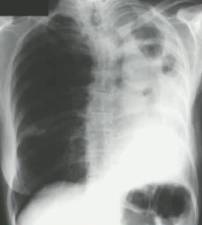

慢性纤维化性肺曲霉病(CFPA):常因未经规范治疗的CCPA发展而来,至少有两个肺叶的严重纤维化破坏,伴肺功能丧失。而单发空洞伴一个肺叶的严重纤维化性破坏,简称为CCPA影响的肺叶。